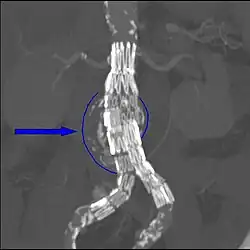

Ein alternatives Verfahren zur offenen konventionellen Operation ist die endovaskuläre Aneurysmatherapie (EAT oder EVAR für endovascular aneurysm bzw. aortic repair) durch Aneurysmaexklusion mittels Aortenstent. Dieser wird über die Femoralgefäße nach proximal in die Aorta platziert und so das Aneurysma ausgeschaltet. Seit der ersten EAT durch Parodi 1991 liegen Erfahrungen mit dieser wenig invasiven Methode bei mehreren tausend Patienten vor. Die publizierten Daten schwächen die anfängliche Euphorie für diese Methode ab. Es zeigt sich einerseits, dass die Platzierung bei einem Großteil der Patienten primär erfolgreich verläuft. Andererseits sind die Systeme keineswegs ausgereift, so dass im Mittel- und Langzeitverlauf die Komplikationsrate nicht unbeträchtlich ist.

Die endovaskulären Prothesensysteme bestehen aus einem selbstexpandierenden Nickel-Titan (= Nitinol)-Skelett, das von einer dünnwandigen Polyester- oder PTFE-Prothese überzogen ist. Dieses System wird auch Stentgraft, Hybridprothese oder gecoverter Stent genannt. Am gebräuchlichsten und in der elektiven Situation fast ausschließlich gebraucht sind modular aufgebaute Bifurkationsprothesen. Das Hauptmodul besteht aus dem Prothesenkörper, einem langen und einem zweiten kurzen Schenkel. Letzterer wird mit einem gesonderten kontralateralen Schenkel ergänzt. Beide Komponenten sind in getrennten Entladungssystemen verpackt. Sie werden über eine Inzision der Leistenarterie eingeführt, unter Röntgendurchleuchtung in das Aneurysma platziert und expandiert. Es sind auch aorto-uni-iliakale Systeme erhältlich, bei welchen die Blutversorgung des kontralateralen Beines über einen Crossover-Bypass erfolgt. Postinterventionell kann der Patient nach einem kurzen Aufenthalt auf der Überwachungsstation auf die Normalstation verlegt werden. Die Entlassung erfolgt nach Kontrolle bezüglich Endoleak (Duplexsonografie und CT) ca. vier Tage nach der Operation. Im Gegensatz zur offenen Operation, bei welcher kaum Nachkontrollen nötig sind, liegt das große Problem der Endoprothesen in der Entwicklung von so genannten Endoleaks (Leckage), die in bis zu 44 % der Fälle auftreten. Durch Endoleaks kommt der Aneurysmasack wieder unter systemischen Blutdruck, so dass das Ziel der Operation nicht erreicht ist. Folgende Endoleaktypen werden unterschieden:[2]